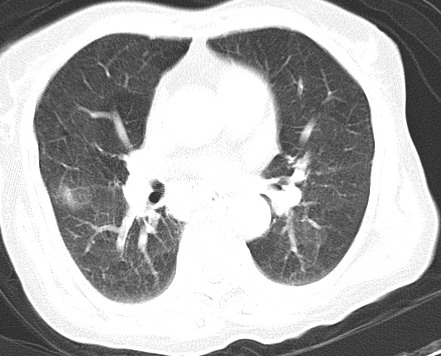

以下是引用hhcckk在2007-3-2 14:51:00的发言:[br]考虑结核球可能性大,依据[br]1病灶在下叶背段,结核的好发部位[br]2病灶内有大量的钙化,纵隔内有大量的淋巴结钙化[br]3重要的是半年前与现在相比无变化,假如是肿瘤的话不会这么‘善良’[br]4病灶周围卫星灶不明显,病灶有毛刺,胸膜凹陷,肿瘤不能完全排除,有条件的话最好做个活检

以下是引用liuyue在2007-3-2 17:15:00的发言:[br]1位置:右上叶后段[br]2性质:大分叶、粗长毛刺、条状斑片状钙化、纵隔多发淋巴结钙化,无强化,故考虑:肺结核灶(陈旧)